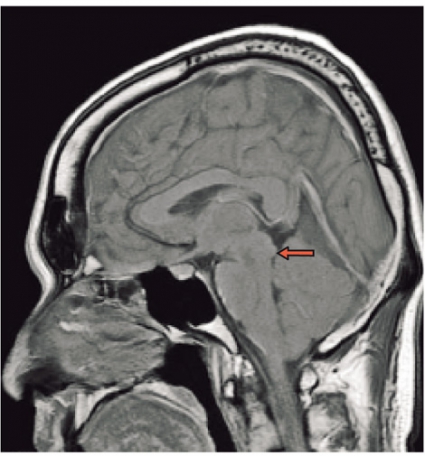

Spontan intrakraniell hypotension är sannolikt ett underdiagnostiserat tillstånd som man bör tänka på hos patienter med nytillkommen daglig huvudvärk, särskilt om den förvärras i stående (Fakta 1). För att ställa diagnos gäller att likvortrycket ska vara lågt, helst <6 cm H2O i liggande, och MRT med kontrast (helst före lumbalpunktion) ska visa generell dural uppladdning (s k pakymeningit) och karakteristiska förändringar av hjärnstammen (Fakta 2) [1, 2]. Initial behandling är symtomlindring med sängläge och gradvis mobilisering. Den kompletteras ofta med rikligt vätskeintag och koffein, antingen i tablettform eller som dropp. Om detta inte ger effekt är epidural injektion av autologt blod (»blood patch«) nästa steg, som ger snabb effekt hos de flesta patienter men som kan behöva upprepas [3]. Vid terapiresistens övervägs utvidgad neuroradiologisk utredning för att lokalisera likvorläckagestället. Då finns möjlighet att upprepa blodinjektionen över själva läckagestället. Om det inte hjälper kan kirurgiskt ingrepp diskuteras [2]. Etiologi och patogenes År 1938 beskrev den tyske läkaren Georg Schaltenbrand det tillstånd som kom att kallas spontan intrakraniell hypotension [4, 5]. Då trodde man att orsaken var minskad produktion av likvor från plexus choroideus eller ökad absorption, men bevis saknades. I dag vet man att tillståndet beror på likvorläckage, sannolikt på grund av en defekt i dura mater. Vid utredning har man kunnat påvisa spinala epidurala cystor (divertiklar) som bedömts ha rupturerat spontant eller vid en plötslig tryckstegring i likvorrummet. Det är också känt att osteofyter och diskbråck kan orsaka läckage genom att erodera duran [6, 7]. I dessa fall kan operation bli nödvändig [8]. Vid kirurgi kan man se många olika durala avvikelser, såsom rifter och meningeala cystor [9-11]. Spontan intrakraniell hypotension uppkommer förmodligen i vissa fall av en kombination av lindrigt trauma och underliggande spinal patologi [2, 12]. Enligt litteraturen har upp till en tredjedel av patienterna en oupptäckt bindvävssjukdom. Många har morfologiska tecken på bindvävssjukdom, såsom lång och smal kroppsbyggnad, spindelfingrar och överrörlighet i lederna [13, 14]. I de flesta fall är dock bindvävssjukdomen ospecifik, och endast i ca 5 procent av fallen har en specifik diagnos kunnat ställas, såsom Marfans syndrom eller Ehlers–Danlos syndrom typ II [13, 15-17]. Familjär spontan intrakraniell hypotension har även beskrivits [18]. Det är viktigt att veta att ett normalt spinalt öppningstryck (7–20 cm H2O) inte utesluter diagnosen [12]. Hos en patient med normalt tryck är det symtomen och tecknen på MRT som ger diagnosen. Många menar att förlust av likvor är den verkliga orsaken till syndromet och att hypotensionen är en följd av hypovolemin [19]. Likvorhypovolemisyndrom (CSF hypovolemia syndrome) har därför föreslagits som ett nytt namn på tillståndet [19]. Läckagestället är nästan alltid beläget i cervikotorakala delen, ofta i cervikotorakala övergången [12]. I praktiken kan det vara svårt att fastställa ett exakt läckageställe. Ofta samlas vätska bakom durasäcken i höjd med kotkropparna C1–C2 [20]. Denna vätskeansamling är dock inte ett säkert tecken på läckage från detta område. Det kan vara en falsk lokalisation. Sannolikt kommer läckaget från en annan nivå, och vätskan förflyttas uppåt till övre halsryggen [20]. Ibland kan man se multipla läckageställen samtidigt [21]. Epidemiologi Spontan intrakraniell hypotension har länge ansetts vara mycket sällsynt. Men kanske är tillståndet inte så ovanligt. Inga säkra siffror från samhällsbaserade studier finns tillgängliga för att beräkna incidensen och prevalensen. I en studie av radiologiska undersökningar på en akutavdelning diagnostiserades sjukdomen ungefär hälften så ofta som spontan subaraknoidalblödning – med en uppskattad årlig incidens på 5/100 000 [22]. På ett sjukhus i Rom diagnostiserades 82 patienter under en 18-årsperiod, 1992–2009, av vilka 40 behandlades konservativt med sängläge och 42 med lumbal epidural injektion av autologt blod [3]. På vår klinik har vi haft 10–15 patienter med detta tillstånd de senaste fyra åren. Den högsta incidensen av spontan intrakraniell hyptension ses vid vid ca 40 års ålder, men fall har beskrivits hos personer mellan 3 och 86 års ålder. Sjukdomen tenderar att drabba kvinnor något oftare än män (kvot ca 1,5:1) [2]. Kliniska symtom Den vanligaste kliniska manifestationen av spontan intrakraniell hypotension är ortostatisk huvudvärk, som förvärras gradvis med maximal intensitet efter flera minuter till timmar. Det händer att huvudvärken debuterar plötsligt. Man misstänker då ofta subaraknoidalblödning, och patienten utreds av denna anledning [23]. De allra flesta patienter kan minnas dagen då huvudvärken började, om än inte den exakta tidpunkten. Huvudvärken brukar beskrivas som diffus, pulserande eller icke-pulserande och är vanligen lokaliserad till nackregionen men kan också vara frontotemporal. Huvudvärken behöver inte vara symmetrisk men är sällan helt ensidig. Hur allvarlig huvudvärken är varierar, och det är troligt att en del lindriga fall förblir oupptäckta och att läkning sker spontant. En ledtråd till diagnosen kan vara om patienten beskriver en dragningskänsla från huvudet ner till nacken. Ytterligare ledtrådar är om patienten föredrar att ligga ned på undersökningsbritsen eller har en kudde med sig [2]. Även om ortostatisk huvudvärk är det kliniska kännetecknet, vilket återspeglas i alla diagnostiska kriterier, är det välkänt att den ortostatiska komponenten ofta blir mindre framträdande eller försvinner med tiden. Dessutom har patienter vars huvudvärk från början har saknat ortostatisk komponent beskrivits [24, 25]. Den exakta orsaken till huvudvärken är inte känd, men man antar att det är förlusten av likvor som orsakar neddragningen av hjärnan med sekundär dragning av smärtkänsliga intrakraniella strukturer [12]. En alternativ förklaring är att det sker en kompensatorisk dilatation av smärtkänsliga intrakraniella venösa strukturer. Förutom huvudvärk har många andra symtom rapporterats. De vanligaste, som förekommer i mer än hälften av fallen, är nacksmärta eller nackstelhet, illamående och kräkningar. Upp till hälften av patienterna beskriver lockkänsla eller tinnitus, och ca 10 procent uppvisar kranialnervspåverkan (vanligtvis abducenspares) med dubbelseende [12]. Abducensnerven har en lång och komplicerad väg intrakraniellt och är därför särskilt utsatt. MRT-undersökning av hjärnan MRT har revolutionerat inte bara erkännandet av sjukdomen utan också förståelsen av den [2]. MRT har i hög grad underlättat möjligheten att komma fram till en säker diagnos utan att behöva använda ingrepp som lumbalpunktion. MRT är förmodligen den viktigaste faktorn bakom det ständigt ökade antalet patienter med spontan intrakraniell hypotension sedan början av 1990-talet [2]. Det typiska fyndet vid cerebral MRT är generell pakymeningit (Figur 1). Pakymeningit i samband med spontan intrakraniell hypotension beskrevs första gången år 1991 av Mokri et al [26]. Det är dock viktigt att veta att upp till 20 procent av patienterna med spontan intrakraniell hypotension inte har någon tydlig pakymeningit [27]. Man tror att den meningeala förtjockningen beror på dural vasodilatation. Grunden för detta är Monroe–Kellie-doktrinen, enligt vilken summan av intrakraniellt blod, likvor och hjärnvävnad ska vara konstant i ett intakt kranium. Det innebär att minskningen av likvor leder till kompensatorisk vasodilatation [12, 19]. De flesta av förändringarna som ses vid MRT kan förklaras av dessa kompensatoriska mekanismer med pakymeningeal uppladdning, vidgning av venösa strukturer och hypofysförstoring. »Sagging«, eller neddragning, av hjärnan är ett typiskt radiologiskt fynd vid spontan intrakraniell hypotension (Figur 2). Det ses tydligast på en sagittal MRT-bild med neddragning av hjärnstam och lillhjärnstonsiller genom foramen magnum som vid Chiari-missbildning typ 1 (Figur 2). Subdural vätska (effusioner och hematom) förekommer hos ca 50 procent av patienterna (Figur 3). Oftast är dessa vätskeansamlingar tunna, bilaterala och lokaliserade till ovanför storhjärnshemisfärerna, orsakade av bristningar i bryggvener, utan någon märkbar expansiv effekt. Vätskeansamling ses ibland i bakre skallgropen, särskilt över lillhjärnshemsifärerna eller bakom clivus. Dessa vätskeansamlingar brukar försvinna när behandling sätts in mot det underliggande spinala likvorläckaget 28]. Om kirurgin riktas endast mot vätskeansamlingarna utan att läckaget behandlas är risken för recidiv ganska stor. Hypofysär hyperemi med förstoring av körteln är ett annat radiologiskt tecken på spontan intrakraniell hypotension [29]. Förstoringen kan bli ganska anslående och kan likna en hypofystumör. Det finns många tillstånd som radiologiskt kan likna spontan intrakraniell hypotension. Den förtjockade kontrastladdade duran kan misstolkas som ett kroniskt subduralhematom, men i dessa fall ses i regel ett vätskespatium mellan uppladdningarna. Idiopatisk hypertrofisk pakymeningit ger oftare fokal, dural förtjockning och inte den jämna, kontinuerliga uppladdningen som vid hypotensionssyndromet. Framför allt gäller detta vid granulomatös meningit och meningeal karcinomatos, vilka också oftare drabbar de mjuka hinnorna än den hårda hjärnhinnan. Meningealt lymfom och durala metastaser liksom meningiom med »dural svans« har ofta associerade skelettförändringar. Vid alla ovan nämnda tillstånd saknas dessutom den typiska bilden av neddragen hjärna. Spinal MRT Spinal MRT kan visa områden med extradural vätskeansamling (särskilt vid C1–C2) (Figur 4 och 5), meningeala divertiklar, dilatation av epidurala vener, dural uppladdning och komprimerad durasäck [30-32]. DT-myelografi Lumbalpunktion med injektion av jodkontrast följt av DT-myelografi med tunna snitt och reformateringar av hela ryggraden har visat sig vara en bra metod för att definiera läckagets exakta lokalisering och omfattning. DT-myelografi har visat sig ha störst känslighet vad gäller att lokalisera läckagestället [32]. Icke-invasiva undersökningar som spinal MRT rekommenderas dock i första hand [33]. Myelografi med intratekal administration av gadolinium följt av MRT är ett alternativ som ibland används utomlands [34] men är ännu inte godkänd på indikationen spontan intrakraniell hypotension i Sverige. Lumbalpunktion Vanligtvis är öppningstrycket <6 cm H2O, och det kan vara omätbart. Det är dock väl dokumenterat att en del patienter med spinalt likvorläckage kan ha ett normalt öppningstryck [33]. Den förhöjda halten av protein och/eller förekomst av xantokromi beror troligen på ökad permeabilitet i dilaterade meningeala blodkärl. Behandling Även om detaljerade uppgifter saknas sker sannolikt spontanläkning i de flesta fall av spontan intrakraniell hypotension. Symtomlindring med sängläge och gradvis mobilisering är en väldokumenterad behandling [12]. Koffein och teofyllin har också visat viss effekt [12]. Om sängläge inte hjälper är den vanliga behandlingen injektion av autologt blod (10–30 ml) epiduralt i ländryggen [35]. Om behandlingen misslyckas kan den upprepas en till två gånger, och man kan då spruta in större mängder blod, upp till 40 ml. Med tanke på den potentiellt stora volymen blod som injiceras rekommenderas några dagars mellanrum vid upprepad behandling. Volymen blod som kan injiceras begränsas huvudsakligen av ryggsmärta eller radikulopati. Det rekommenderas att patienten bibehåller planläge efter injektionen för att minska likvorflödet genom duradefekten och därmed hjälpa till att stänga hålet. Det har diskuterats om injektion av autologt blod verkligen hjälper när läckagestället är på cervikotorakal nivå. En del rapporter finns som visar att behandlingen är effektiv [36, 37]. I den tidigare nämnda studien från Rom [3] behandlades 42 patienter med spontan intrakraniell hypotension på dettta sätt med stor framgång, trots att läckaget i de flesta fall var på cervikotorakal nivå. 38 patienter (90 procent) blev återställda efter ett ingrepp, 2 patienter (5 procent) efter två ingrepp och 2 patienter (5 procent) efter tre ingrepp. Författarna rekommenderar dock konservativ behandling under tio dagar innan blodinjektion ges. Romgruppen lät patienterna ligga i Trendelenburgläge 1 timme före och 24 timmar efter ingreppet. Intressant nog behandlade de patienterna med acetazolamid, 250 mg i tablettform, 18 och 6 timmar före ingreppet. Acetazolamid är en karbanhydrashämmare som minskar produktionen av likvor. Romgruppen för ett resonemang om huruvida premedicineringen och långvarigt Trendelenburgläge kan minska likvorflödet genom duradefekten och därmed hjälpa till att stänga hålet. Dessutom kan premedicineringen minska risken för återuppkomst av tillståndet [38]. Om den lumbala blodinjektionen inte hjälper kan man försöka injicera blod eller fibrinlim (Tissel) direkt över läckagestället. Dessa behandlingar kräver att läckagestället är känt. Placering av fibrinlim ger förmodligen den bästa symtomlindrande effekten [39]. När konservativ behandling och blod eller fibrinlim inte ger effekt kan kirurgi vara ett alternativ [8, 12]. Kirurgi innebär bl a ligering av meningeala divertiklar, packning med spongostan, fibrinlim eller gelskum i epidurala rummet, suturering av durarifter samt resektion av osteofyter och diskbråck. Prognos Långtidsuppföljningarna av naturalförlopp och behandlingsresultat är knapphändiga, men spontan intrakraniell hypotension tros återkomma hos ca 10 procent, oavsett behandling. Patienter med en radiologisk bild som är typisk för spontan intrakraniell hypotension och med känt läckageställe har utmärkt prognos, medan personer med normal MRT-undersökning och diffus spinalt likvorläckage på flera nivåer tycks ha sämre prognos [2]. Vissa patienter har kvarstående symtom efter behandling trots dokumenterat upphävt likvorläckage. Dessa patienter är svåra att behandla, och det är oklart om de har förändrad likvordynamik eller kanske små rester av likvorläckage som inte syns på röntgenbilder. * Potentiella bindningar eller jävsförhållanden: Inga uppgivna.